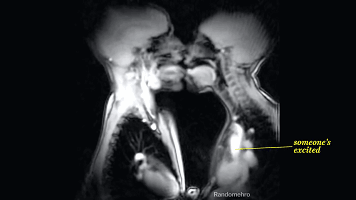

从下图可以看出,两个人的舌头都开始不老实了。

接吻会加剧兴奋,会使心跳速度进一步增加,呼吸也会更急促,全身的肌肉开始出现不规则的收缩肌紧张。

(有人兴奋了…)